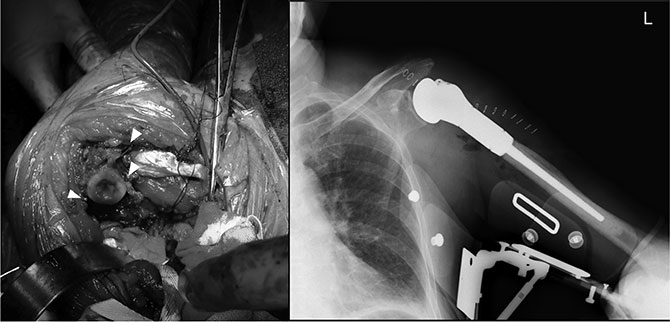

张余主任(右一)在镁夹具植入前进行右肱骨病灶的肿瘤外切除

手术由骨肿瘤科张余主任和黄文汉主治医师等共同完成。术中完整切除患者左肱骨近端肿瘤段骨骼共计9cm,在截骨面周围的小血管、骨膜、肌肉等切缘处进行环形镁合金夹植入和标记,而后安装组配式肿瘤型人工肩关节假体。历经4小时,让患者恢复了肩关节的外展、屈曲功能。目前,患者已顺利出院。

镁夹具夹闭截骨面周围骨膜切缘的环形植入的镁夹(左图)

术后复查正肩关节假体位置良好(右图)